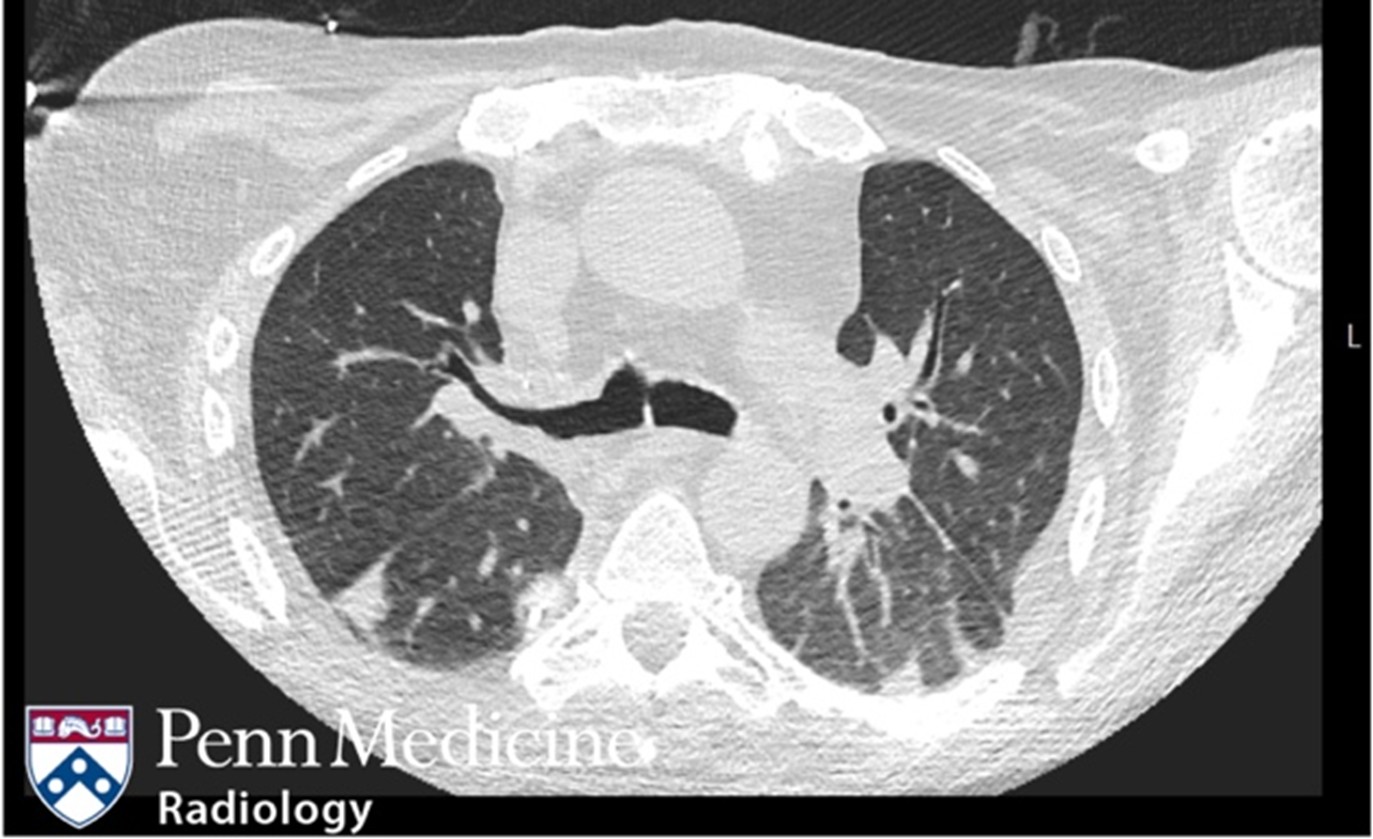

Cases of the Week

Check out our Cases of the Week!